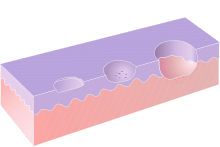

An ulcer (/ˈʌlsər/; from Latin ulcus, "ulcer, sore")[2] is a break in the skin or mucous membrane with loss of surface tissue and the disintegration and necrosis of epithelial tissue.[3] A mucosal ulcer is an ulcer which specifically occurs on a mucous membrane. An ulcer is a tissue defect which has penetrated the epithelial-connective tissue border, with its base at a deep level in the submucosa, or even within muscle or periosteum.[4] An ulcer is a deeper breach of the epithelium than an erosion or an excoriation, and involves damage to both epithelium and lamina propria.[5]

An erosion is a superficial breach of the epithelium, with little damage to the underlying lamina propria.[5] A mucosal erosion is an erosion which specifically occurs on a mucous membrane. Only the superficial epithelial cells of the epidermis or of the mucosa are lost, and the lesion can reach the depth of the basement membrane.[4] Erosions heal without scar formation.[4]

Excoriation is a term sometimes used to describe a breach of the epithelium which is deeper than an erosion but shallower than an ulcer. This type of lesion is tangential to the rete pegs and shows punctiform (small pinhead spots) bleeding, caused by exposed capillary loops.[4]

Erosions, which involve the epithelial layer, are red in appearance since the underlying lamina propria shows through. When the full thickness of the epithelium is penetrated (ulceration), the lesion becomes covered with a fibrinous exudate and takes on a yellow-grey color. Because an ulcer is a breach of the normal lining, when seen in cross section, the lesion is a crater. A "halo" may be present, which is a reddening of the surrounding mucosa and is caused by inflammation. There may also be edema (swelling) around the ulcer. Chronic trauma may produce an ulcer with a keratotic (white, thickened mucosa) margin.[5] Malignant lesions may ulcerate either because the tumor infiltrates the mucosa from adjacent tissues, or because the lesion originates within the mucosa itself, and the disorganized growth leads to a break in the normal architecture of the lining tissues. Repeat episodes of mouth ulcers can be indicative of an immunodeficiency, signaling low levels of immunoglobulin in the oral mucous membranes. Chemotherapy, HIV, and mononucleosis are all causes of immunodeficiency/immunosuppression with which oral ulcers may become a common manifestation. Autoimmunity is also a cause of oral ulceration. Mucous membrane pemphigoid, an autoimmune reaction to the epithelial basement membrane, causes desquamation/ulceration of the oral mucosa. Numerous aphthous ulcers could be indicative of an inflammatory autoimmune disease called Behçet's disease. This can later involve skin lesions and uveitis in the eyes. Vitamin C deficiency may lead to scurvy which impairs wound healing, which can contribute to ulcer formation.[8] For a detailed discussion of the pathophysiology of aphthous stomatitis, see Aphthous stomatitis#Causes.